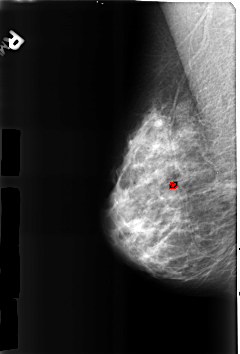

B_3184_1.RIGHT_MLO

RIGHT_MLO LINES 4600 PIXELS_PER_LINE 3112 BITS_PER_PIXEL 12 RESOLUTION 50 OVERLAY

FILE: B_3184_1.RIGHT_MLO.OVERLAY

TOTAL_ABNORMALITIES 1

ABNORMALITY 1

LESION_TYPE CALCIFICATION TYPE LUCENT_CENTER DISTRIBUTION N/A

ASSESSMENT 2

SUBTLETY 3

PATHOLOGY BENIGN_WITHOUT_CALLBACK

TOTAL_OUTLINES 1

BOUNDARY